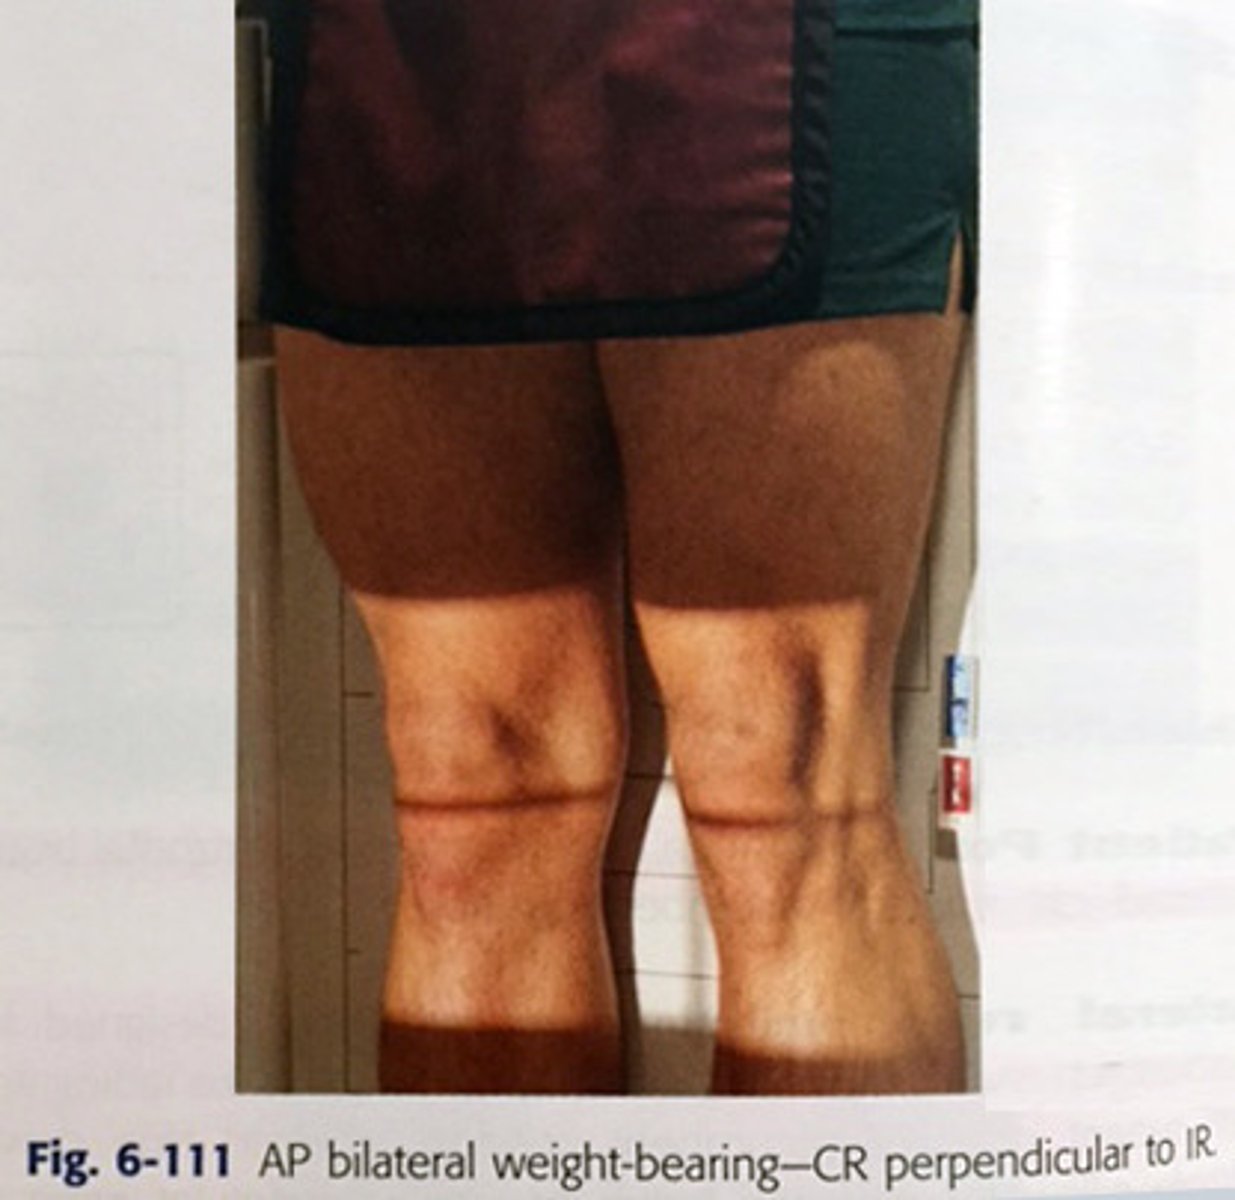

Describe, in detail, the positioning of the PATIENT for an AP KNEE WEIGHT-BEARING projection.

1. Patient stands with the posterior aspect of the knee joint in contact with the upright bucky (no grid required).

2. Patient's weight should be evenly distributed.

3. The lower leg is rotated until the patella is centralised and the femoral condyles equidistant to the IR.

4. Make sure that the patient's leg is fully extended and that they are standing up straight against the bucky.